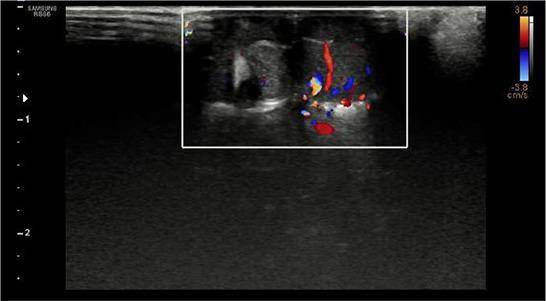

A 3-year-old, 420 g, intact male African pygmy hedgehog () was presented with a sudden appearance of a mass protruding from its preputium. A detailed physical examination revealed the presence of a polyp-like mass, connected to the mucous membrane of the penis and a second, multilobular mass with a larger base. Both masses were surgically removed. While the histopathological examination of the polyp-like mass revealed only a chronic active inflammatory reaction, the histopathological examination of the multilobular mass revealed a tumorous tissue composed of spindle-shaped cells, irregularly oval or polygonal in some places. Focal tumour cells with a myxoid differentiation were observed in the greater part of this tumour. The stroma was made up of sparse fibrous tissue. The surface epithelium was hyperplastic with ulcerations and necrosis. The tumour was classified as a myxofibrosarcoma. Two weeks post-surgery, the patient did not show any clinical signs of the presented disease. According to our knowledge, this is the first published case of the surgical treatment of penile myxofibrosarcoma in an African pygmy hedgehog.

一只3岁、体重420克的完整雄性非洲侏儒刺猬被送来就诊,其阴茎突然出现一个肿物。详细的体格检查发现有一个息肉样肿物,与阴茎黏膜相连,还有一个基部较大的多叶状肿物。两个肿物均通过手术切除。息肉样肿物的组织病理学检查仅显示慢性活动性炎症反应,而多叶状肿物的组织病理学检查显示为肿瘤组织,由梭形细胞组成,有些地方呈不规则椭圆形或多边形。在该肿瘤的大部分区域观察到有黏液样分化的局灶性肿瘤细胞。间质由稀疏的纤维组织构成。表面上皮增生,伴有溃疡和坏死。该肿瘤被分类为黏液纤维肉瘤。术后两周,患者未表现出所患疾病的任何临床症状。据我们所知,这是首次发表的关于非洲侏儒刺猬阴茎黏液纤维肉瘤手术治疗的病例。